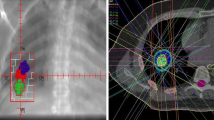

Our treatment methods were described in detail previously [13, 15]. We used the BodyFIX system (Medical Intelligence, Schwabmuenchen, Germany) for patient immobilization. The visible gross tumor volume on CT during three phases (normal breathing and breath holding during the expiratory and inspiratory phases) was superimposed to represent the internal target volume (ITV). Breath-holding-phase CT images were used to ensure the range of tumor motion. During the first study, we had confirmed that a forced inspiration/expiration breath hold would not overestimate the tumor motion and therewith systematically overestimate the margins, by using fluoroscopy [17]. The planning target volume (PTV) margin for the ITV was 5 mm in the lateral and anteroposterior directions and 5–10 mm in the craniocaudal direction. Forward planning was performed using a 3-dimensional treatment planning system (Eclipse Version 7.5.14.3, Varian Medical Systems, Palo Alto, California, USA). Fixed 3 coplanar and 4 non-coplanar beams were used in all cases.

For verification of tumor positions, we used the simulator CT at the first and third treatments in addition to megavoltage portal imaging at every treatment throughout the study period. The patients underwent registration in the CT simulator room, and repositioning was performed whenever necessary. Then, they were carefully transferred to the linac room with a stretcher. SBRT was delivered by CLINAC 23EX (Varian Medical Systems, Palo Alto, California, USA) with 6-MV photon beams and it was delivered with 4 fractions. In principle, the respective fractions were delivered at intervals of ≥ 72 h to allow reoxygenation of hypoxic tumor cells [14], but owing to national holidays, patient schedule convenience, and machine availability, the actual overall treatment period was 8–20 days (median, 11 days). The total dose at the isocenter was increased to 48 Gy for tumors with a maximum diameter < 1.5 cm and 50 Gy for tumors of 1.5–3 cm. For those > 3 cm, the total dose remained at 52 Gy. The dose calculation algorithm was AAA.

It was recommended to cover 95% of the PTV with at least 90% of the isocenter dose, and, in all cases, 95% of the PTV received at least 80% of the prescribed dose. However, the dose was 79.2% in one case. Dose constraints for normal tissues were: (1) volume of the lung receiving 20 Gy, ≤ 20%; (2) 40 Gy for < 1 cm3 of the pulmonary artery and esophagus; (3) 36 Gy for < 10 cm3 of the stomach; and (4) maximum cord dose < 18 Gy, in accordance with the first study [13, 14].